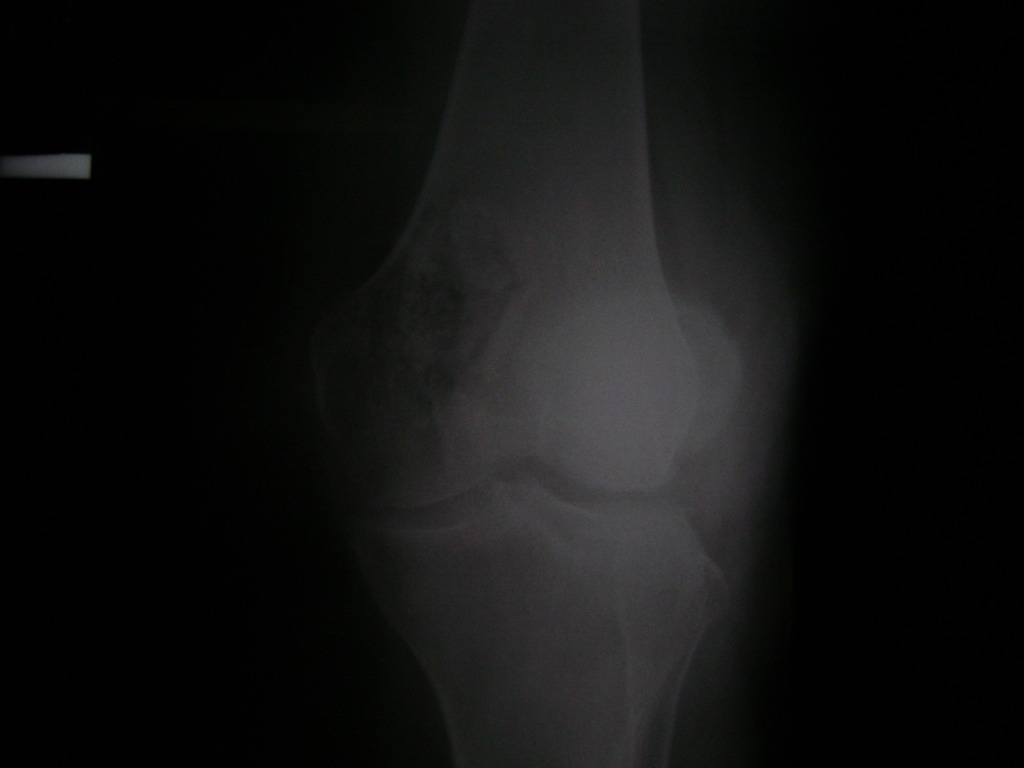

Cirugía de Rodillas